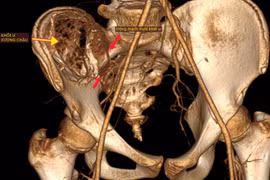

Nút mạch lấy u máu khổng lồ trong xương chậu cho trẻ 12 tuổi

(khoahocdoisong.vn) - Chỉ nghĩ con bị đau xương tuổi dậy thì nào ngờ trẻ 12 tuổi bị  u máu khổng lồ phá hủy nửa cánh xương chậu và đe dọa tính mạng. Nhờ kỹ thuật nút mạch và ghép xương, các bác sĩ tại hai bệnh viện kết hợp đã loại bỏ thành công khối u máu và trám xương thành công cho trẻ.